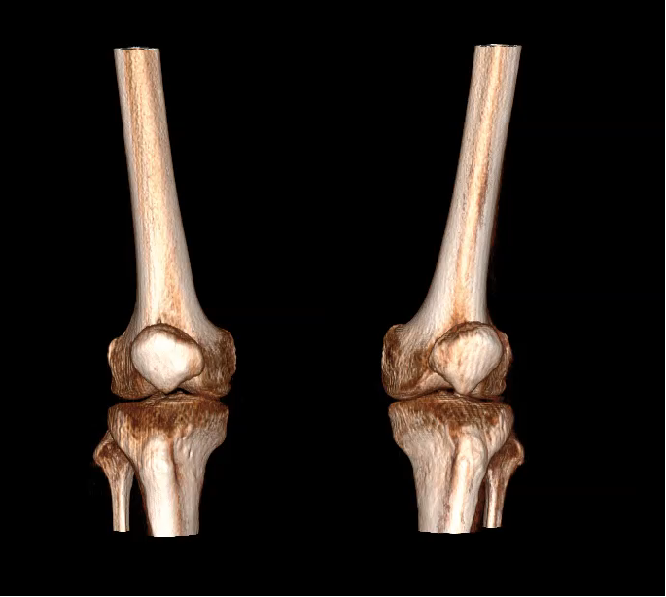

VR体绘制图像

对于WR-3D技术的问世,主要解决了两大核心问题:1、解决了普放DR漏诊率高的现状,常规DR设备仅有某一角度的二维影像、密度信息极差,而WR-3D能获得更丰富的诊断信息,多角度拍摄三维重建影像,任意角度任意切面以及高敏感的密度信息;2、解决了CT无法获得立位(负重位)的三维影像,WR-3D无论是在断层图像重建、MPR多平面重建、VR体绘制都有着优异的表现,而对于临床诊断尤其是骨科,负重位的影像更具有临床价值。患者在负重位状态下肌肉状态、关节间隙及骨骼力线等都与患者平躺时是明显不同的。因此WR-3D在术前精准规划与术后精准评估方面有其非常重要的临床价值。